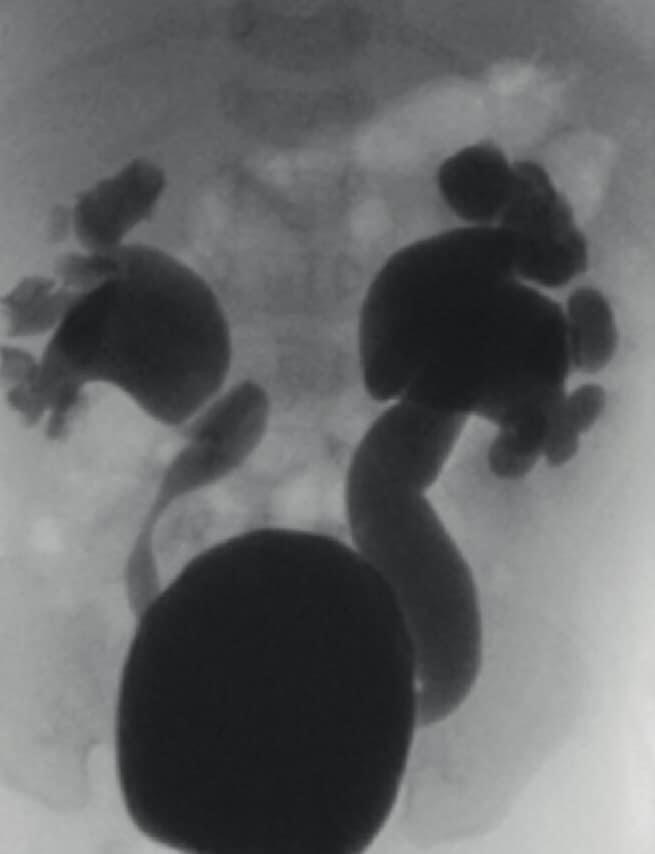

Mərkəzi Klinikanın uzman uşaq cərrahı Fuad Hüseynov Aztibb.az-a bildirib ki, müayinələr zamanı körpəni bu vəziyyətə salan səbəbin böyrəklərdə ciddi genişlənmə olduğu ortaya çıxıb. Böyrəklərdəki genişlənmənin səbəbi isə sidiyin böyrəyə əks istiqamətdə geri qayıtması (grade 5 VUR) olub:

İlkin olaraq, böyrəyi qorumaq üçün sidik axarı müvəqqəti qarnın ön divarına çıxarıldı (Üreterostoma). Körpə qızı qoruma altına alıb böyüməsini gözlədik. 1 yaşı tamam olanda isə sidiyin geriyə qayıtmasının qarşısını almaq məqsədilə cərrahi əməliyyat (Üreteroneosistostomiya) icra etdik".